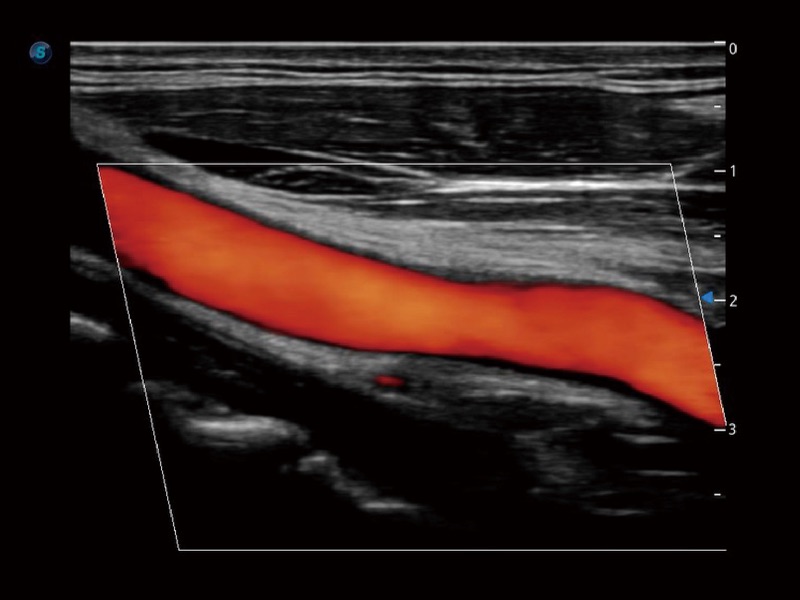

• SR Flow 高分辨率血流成像技术

高分辨率血流成像技术提高了对低速血流信号的检测能力。在提高空间分辨率的同时,也克服了血流外溢现象,为用户提供更加真实的血流动力学信息。